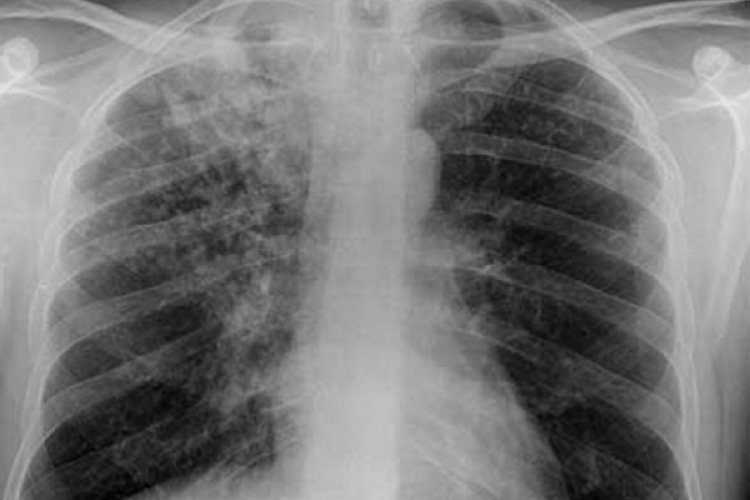

Ежедневно в мире почти 28 тысяч человек заболевают туберкулёзом, который возможно предотвращать и излечивать от него. Благодаря глобальным усилиям по борьбе с туберкулёзом, начиная с 2000 года, было спасено примерно 63 миллиона жизней. В Республике Молдова туберкулёз остаётся одной из приоритетных проблем общественного здравоохранения. В период пандемии COVID-19 отмечается сокращение на 38,7% количества уведомлений о случаях туберкулёза по сравнению с 2019 годом, передаёт IPN.

Согласно сообщению Министерства здравоохранения, труда и социальной защиты, количество новых случаев и рецидивов туберкулёза в 2020 году составило 43,9 на 100 тысяч населения (1762 случая). В 2019 году этот показатель составил 71,6 на 100 тысяч населения (2877 случаев).